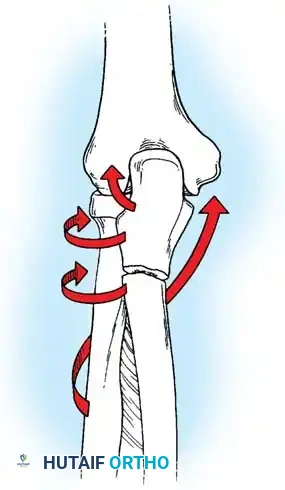

Biomechanics of the Tension Band:

The superficial (posterior) surface of the olecranon is the tension side of the bone. A figure-of-eight wire placed on this surface converts the tensile forces generated by the triceps into compressive forces across the articular fracture line, utilizing the humeral trochlea as a fulcrum.

Surgical Warning: A simple wire loop is biomechanically inferior to a figure-of-eight loop. If a simple loop is used—especially if its axis lies anterior to the mid-axis of the olecranon—the pull of the triceps will cause the fragments to separate posteriorly, leading to articular step-off and limited extension.